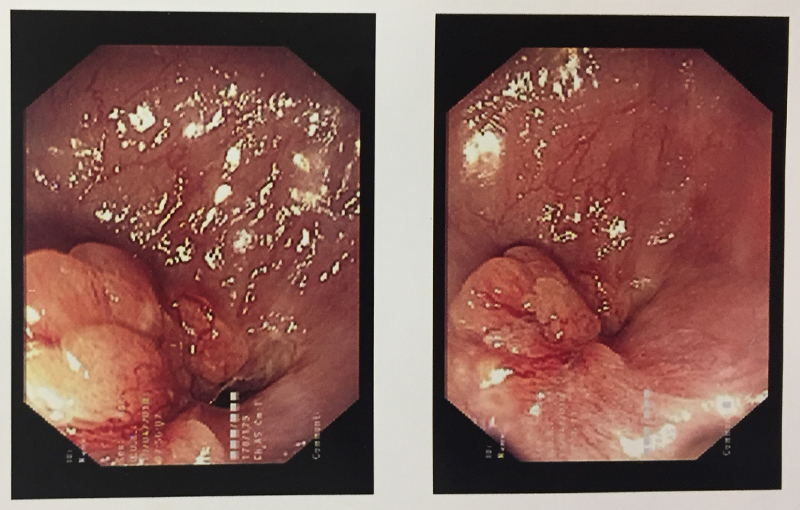

When a stomach cancer is suspected in any patient, he/she is subjected to an endoscopy of the stomach (internal visualization). This helps in diagnosis and taking a biopsy for confirmation. A CT scan is performed after the confirmation (though often patients come with a CT scan diagnosis) to see whether the cancer can be removed surgically. A PET-CT is performed prior to any therapy to see the spread / extent / stage of the disease. If the tumor is in early stage, stomach (part / full depending on which part of stomach is involved and extent) along with the tumor and surrounding lymph nodes is removed and small intestine is joined with the proximal stomach or esophagus. If the tumor is small and lymph node spread is less, this operation is done laparoscopically. A chemoport may also be placed at this time for postoperative chemotherapy (adjuvant) unless it is a very early stage disease. Very early stage cancer can sometimes be removed through an endoscopic procedure (endoscopic mucosal resection --EMR / endoscopic submucosal dissection – ESD) under the guidance of an endoscopic ultrasound equipment. Unfortunately this is very rarely possible in Indian patients since disease is advanced by the time it is diagnosed.

If the disease is diagnosed at a stage where it is advanced in the stomach walls and surrounding region with large lymph nodes then a preoperative (neoadjuvant) chemotherapy is given to downstage the disease. If this attempt is successful and tumor responds, then in that case a curative surgery is done. This is followed by further chemotherapy cycles. Occasionally external radiotherapy is given too. This kind of multidisciplinary treatment plan was used in the above case.